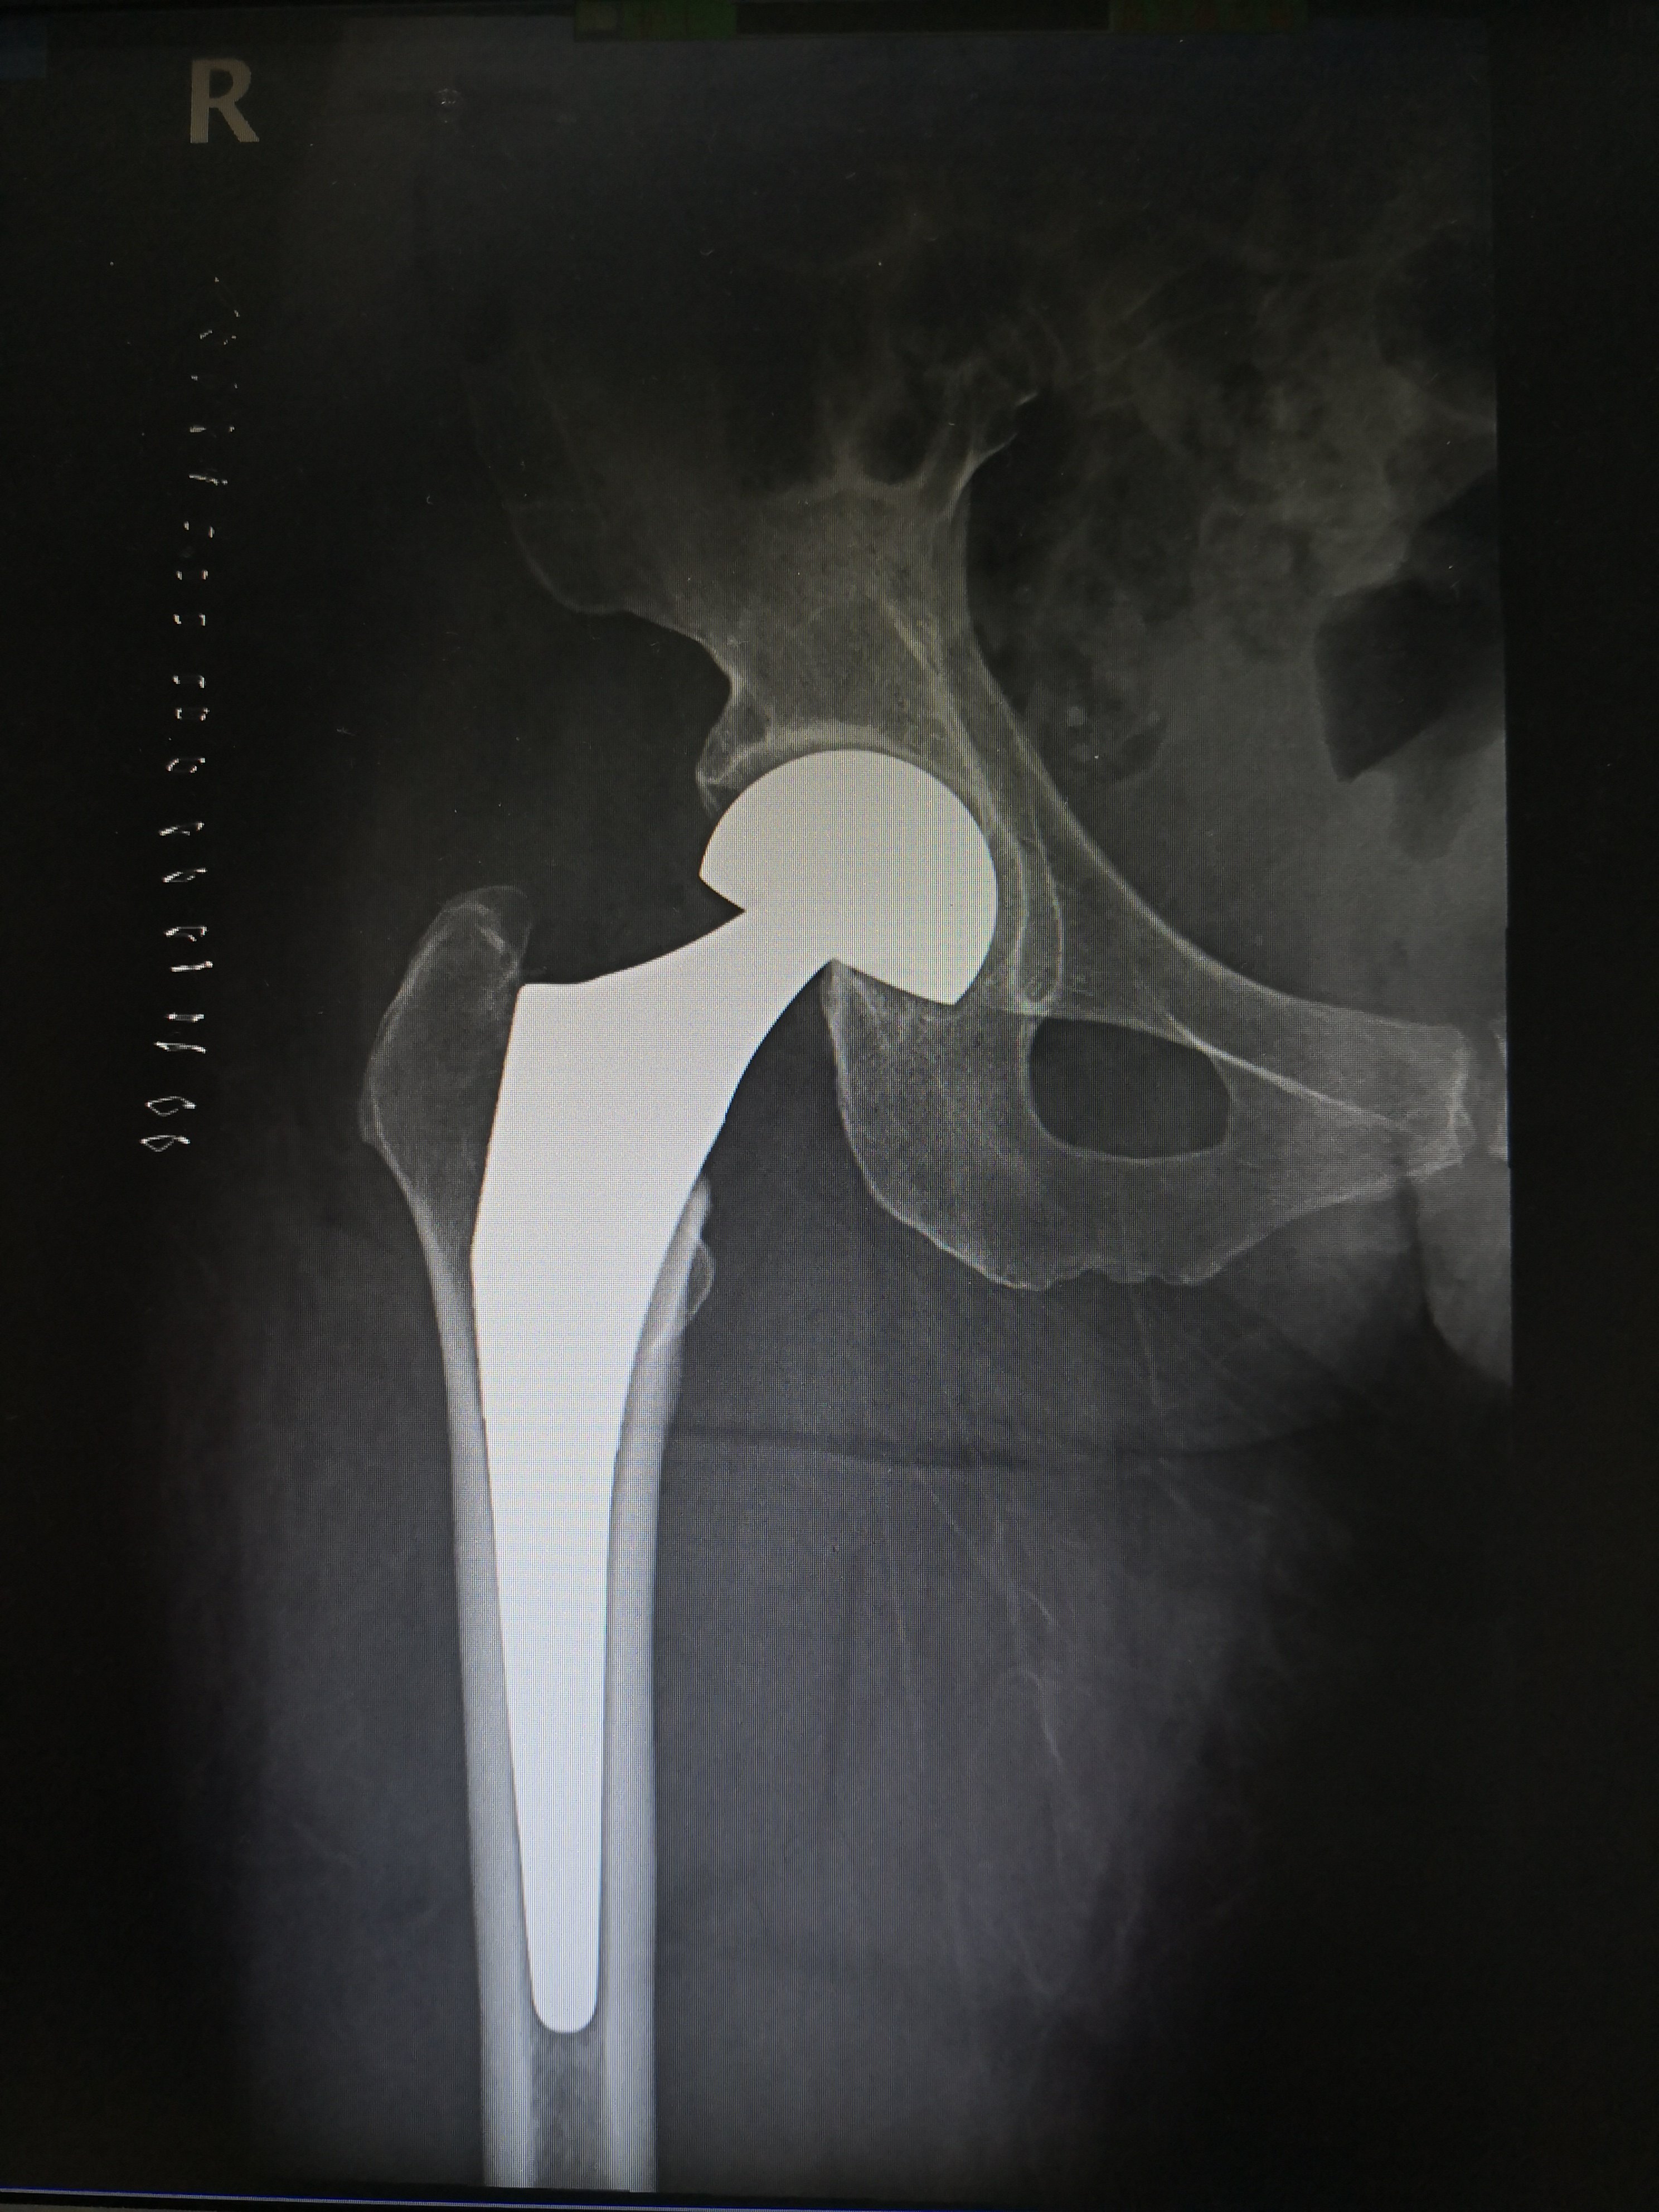

术后人工半髋关节

IMG_20190323_185125.jpg